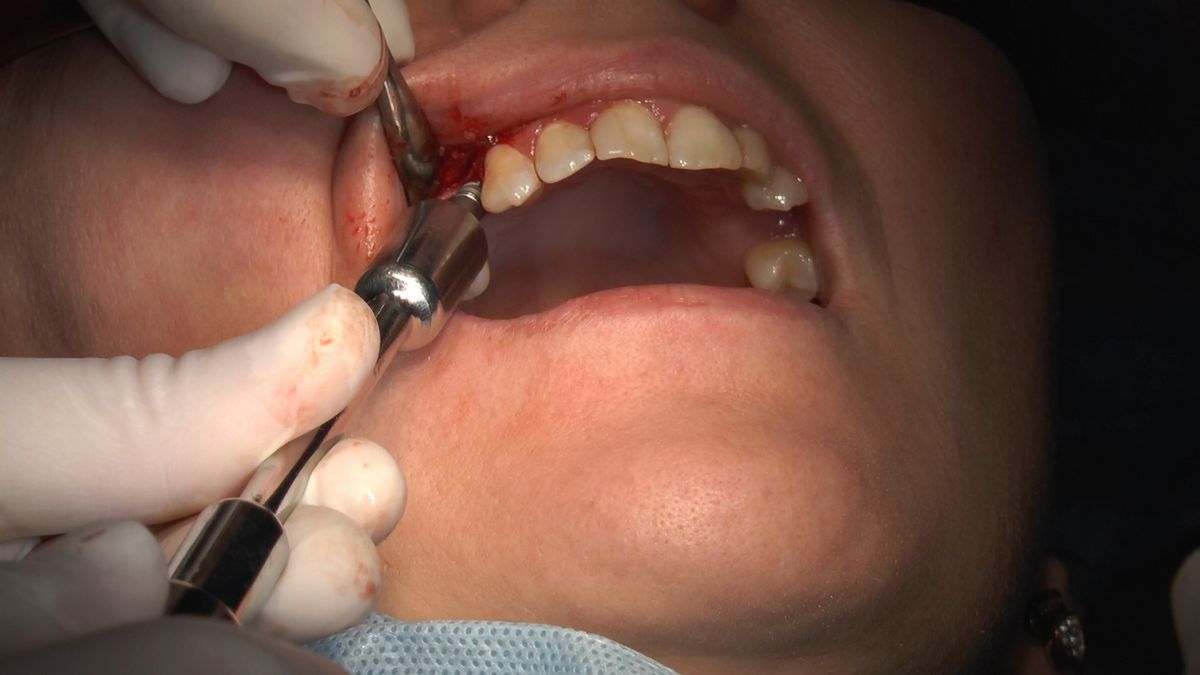

W ostatni weekend czerwca 2018 roku kursanci II Sezonu Preludium Implantologii odbyli piątą, finałową sesję, która w całości podporządkowana była praktyce. W ciągu dwóch dni zabiegowych Lekarze uczestniczący w szkoleniu przeprowadzili szereg zabiegów pod kierunkiem dr n.med. Violetty Szycik. Wszczepili 17 implantów oraz przeprowadzili ekstrakcje i zabiegi regeneracyjne kości. Zabiegi były wykonywane także w sedacji dożylnej z udziałem specjalisty anestezjologii i intensywnej terapii dr Jolanty Grzybowskiej. Preludium implantologii to nowy program edukacyjny dla adeptów implantologii stomatologicznej, którego celem jest wprowadzenie do implantologii poprzez pozyskanie wiedzy w szerokim zakresie i uwzględnieniem szczegółów mających decydujące znaczenie dla powodzenia leczenia implantologicznego. Ale tak jak wszystkie szkolenia w Instytucie Vivadental, w tym wiodące Practiculum Implantologii, zorientowane jest na praktyce i samodzielnym wykonywaniu zabiegów pod kierunkiem Mentora. To najlepsza edukacja w medycynie zabiegowej, a zarazem najlepszy start do implantologii.